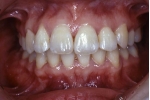

| マルチブラケット終了時